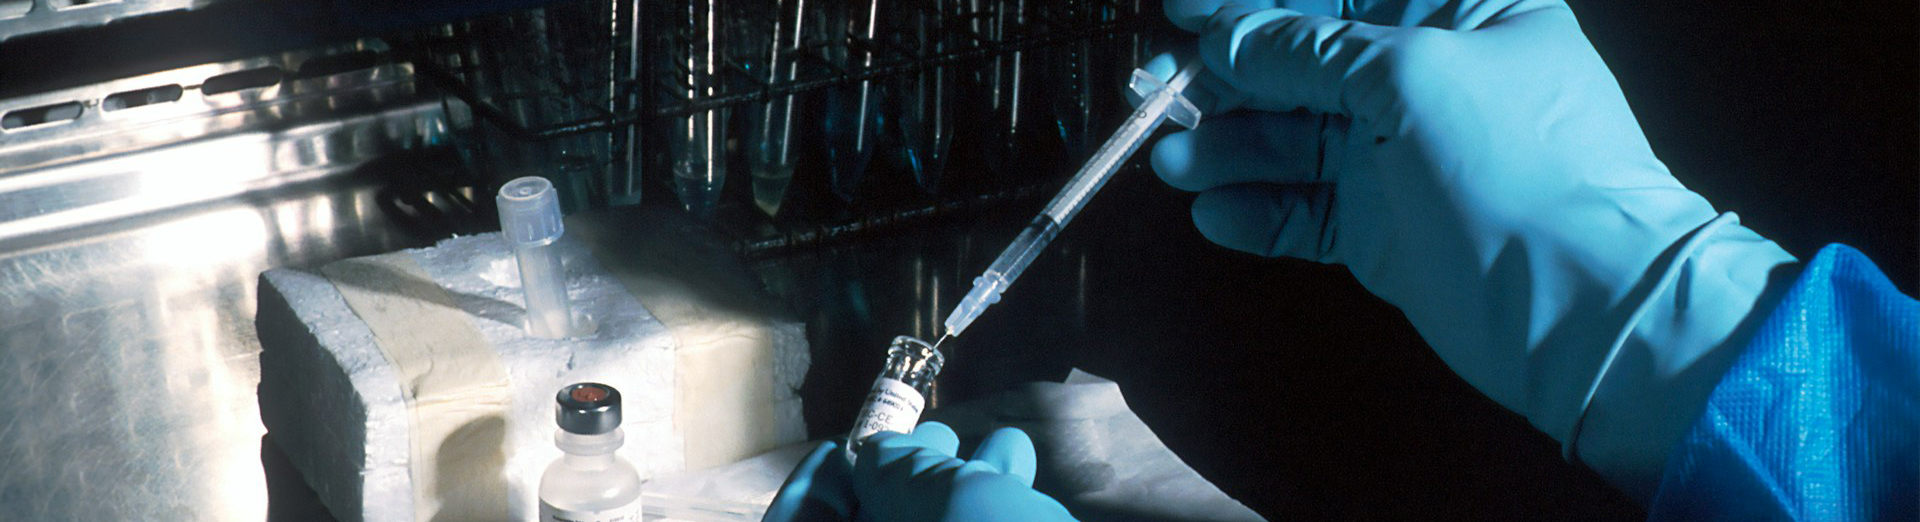

탈모방지 또는 발모촉진용 주사용 조성물

특허출원번호 1020190114935

주사용 의료기기 및 전문의약품 개발을 통해

상피 기반 질환 전반을 아우르는 파이프라인을

구축하고 글로벌 바이오 솔루션 기업으로 성장하고자 합니다.